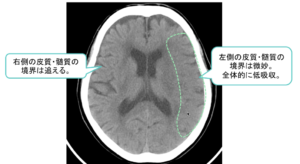

| ③ | ③皮髄境界・島皮質の不鮮明化といった浮腫性変化が発症後2~3時間で出現![]() ![]() |